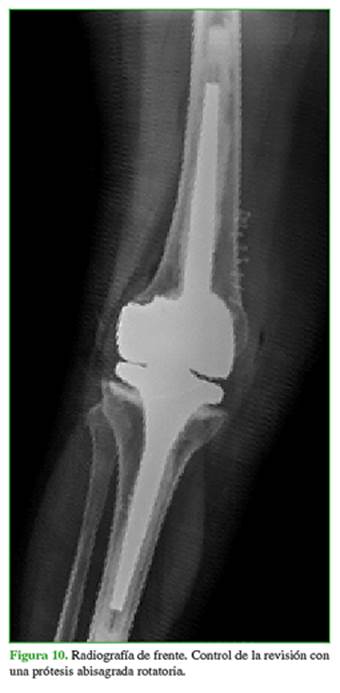

Concurrió a nuestro centro en marzo de 2016 (aproximadamente 2 años después de la intervención) por inestabilidad de la prótesis en recurvatum que le impedía la marcha; no refirió un antecedente traumático (Figuras 8 y 9).

En abril de 2016, se procedió a la revisión de la prótesis y se colocó una prótesis abisagrada rotatoria Endo-Model®. La paciente ha tenido una buena evolución hasta la fecha (34 meses poscirugía) (Figuras 10 y 11).